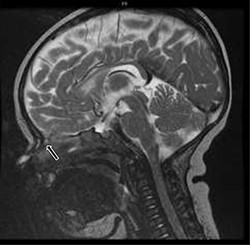

A total of fourteen patients were identified. The age range of these patients was 6 months to 17 years. There was an equal gender distribution. An average of 11 weeks lapsed between initial presentation and definitive excision. All patients underwent MRI; all patients exhibited an abnormality, most commonly isointense T1 and hyperintense T2 soft tissue findings in the area of the nasal dorsum/glabella (Fig. 2). Eleven of the fourteen patients (78.6%) underwent a CT. Of those eleven patients, two patients exhibited a splaying of nasal bones (Fig. 3). Fifty percent of the patients required preoperative antibiotics for infected nasal dermoid cysts; one patient was admitted to the infectious disease service for intravenous antibiotic therapy prior to formal surgical excision. One of the fourteen patients (7.1%) had a formal excision with a rhinoplasty approach, while the majority thirteen of the fourteen patients (92.8%) underwent an open vertical incision for the surgical approach. Four of the fourteen patients (28.5%) had recurrent infection and required additional surgery. Three of seven patients required incision and drainage prior to definitive excision. One of seven patients in the infected group had recurrence. Three of the seven patients in the non-infected group recurred. Bacterial cultures in all of these patients did not identify common pathogens. Surgical pathology revealed acute on chronic inflammation in 50% of cases; three of the fourteen patients (21.4%) revealed multinucleated giant cells on microscopic analysis. Two of the fourteen total patients had intracranial extension. None of these patients developed meningitis.

T2-weighted sagittal MRI of hyperintense soft tissue findings in the setting of a nasal dermoid cyst penetrating the anterior cranial fossa.